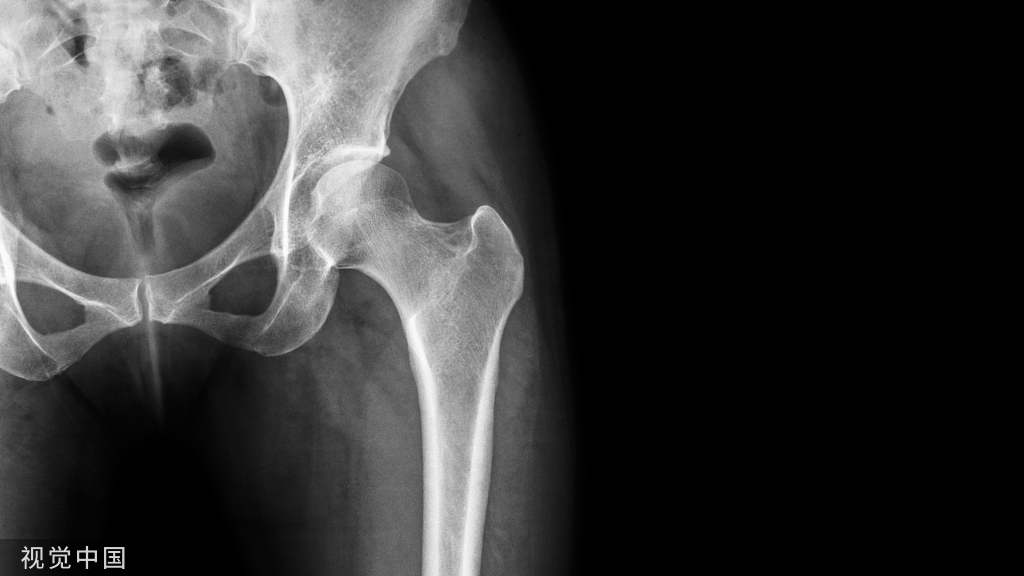

二、Cage支撑技术

Cage支撑技术广泛应用于骨质疏松性骨折的复位固定,如肱骨近端骨折等。同理,该技术也可应用于骨质疏松性桡骨远端骨折。理论上,在最小的软组织剥离情况下,复位后经有限切口置入Cage支撑,实现髓内支撑及有效的软骨下支撑,并辅助螺钉固定。但该技术对骨量条件良好患者可能并不适用,且内植物取除困难。